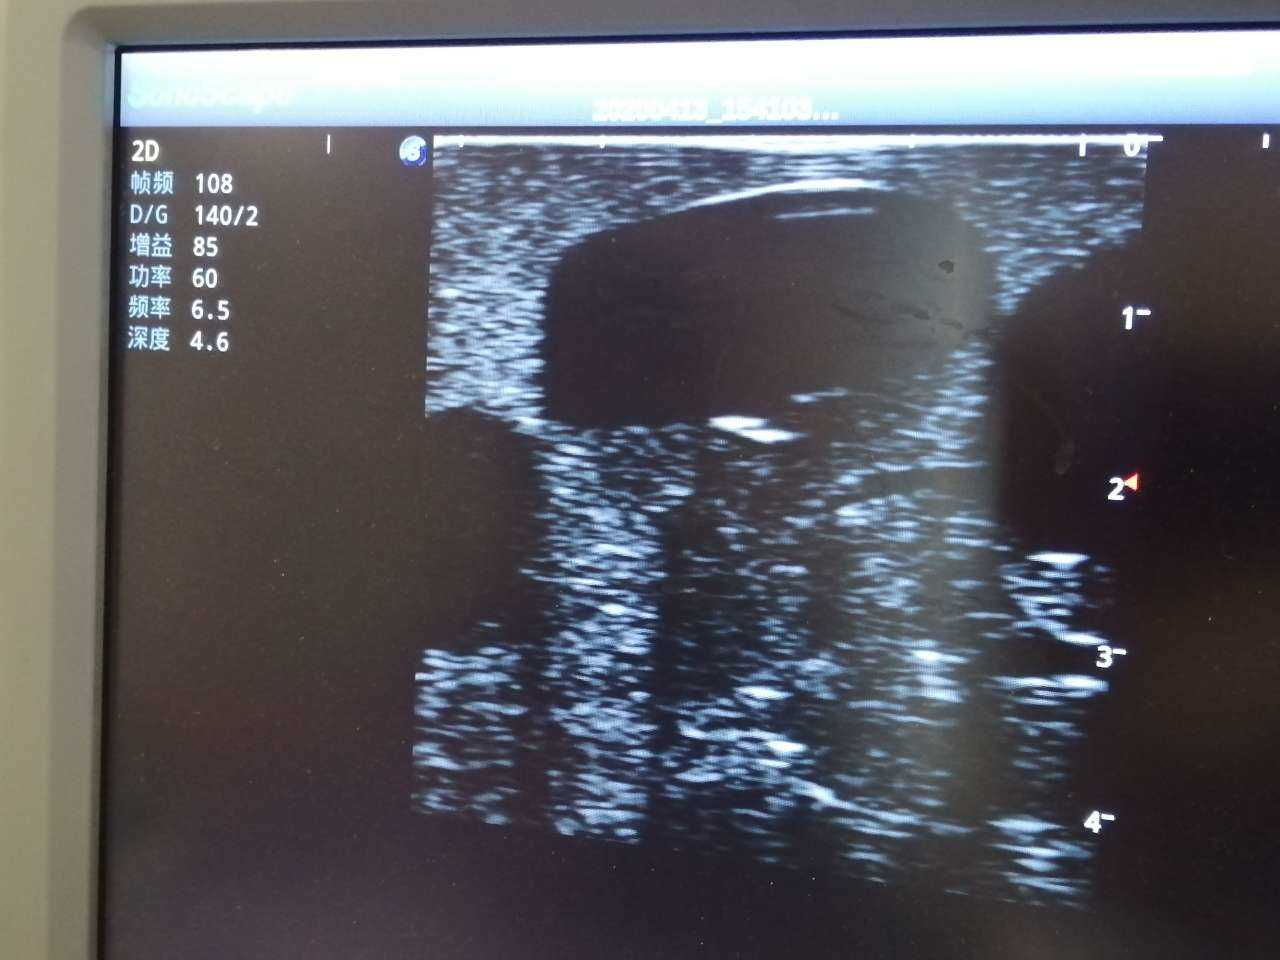

Abscess Drainage Ultrasound Trainer

The trainer is designed for abscess ultrasound recognition, drainage, surgical cutting & suturing. With realistic landmarks and high-quality images, it’s an excellent choice for abscess-related skill training and practice.

· High-quality ultrasound images to show skin, soft tissues, abscess cavity and pus